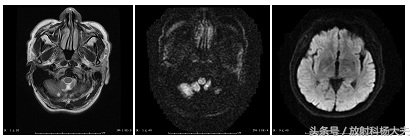

伪影较轻的假牙图像

上文中可以发现,在伪影较重的图像中,DWI图像受到了严重的影响,不利于疾病的诊断与鉴别诊断。